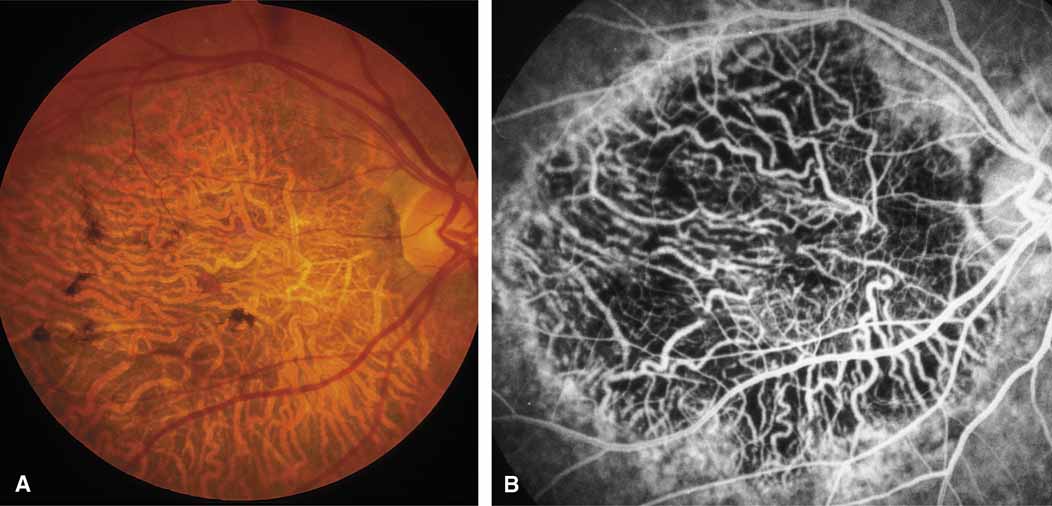

Sorsby's fundus dystrophy (MIM No. 136900), previously called Sorsby's pseudoinflammatory macular dystrophy, is a highly penetrant, autosomal dominantly inherited disorder characterized by a tritan color vision defect, drusen-like subretinal deposits, and pigment epithelial atrophy in younger individuals followed by choroidal neovascularization, hemorrhage, subretinal fibrosis, and choroidal atrophy in later years (Fig. 7).14,36–38 Loss of vision usually commences after the age of 50 years. The disease in late stages progresses to involve the peripheral retina. More recent studies of members of Sorsby's original family demonstrated angioid streaks and yellow plaque-like subretinal deposits, features distinguishing this disorder from dominant drusen.39,40 Visual prognosis is poor because of the tendency of the disease process to involve the macula. The ERG is generally normal except in the most advanced stages when extensive areas of the retina are involved.41 Linkage studies assigned the gene for Sorsby's dystrophy to 22q13-qter.42 Weber et al.43 found mutations in the gene for the tissue inhibitor of metalloproteinase-3 (TIMP3), which is located on the long arm of chromosome 22, in patients with Sorsby's fundus dystrophy. This finding suggests that a defect in maintenance and renewal of Bruch's membrane by the altered gene product is an important underlying pathologic event in Sorsby's fundus dystrophy.